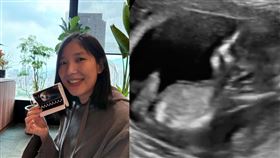

凍卵14顆全淘汰!Sandra最後一搏奇蹟當媽

號稱「全台最紅英文老師」的Sandra(徐有潔)20...

2026/01/03 19:19